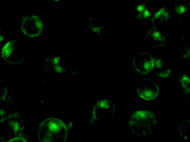

The natural killer cells, also commonly known as the NK cells are the lymphocytes or the fighter cells of the immune system; which are primarily recruited by the...

Natural Killer Cells commonly referred to as NK Cells are a type of innate lymphocyte which aid the immune system by killing virally infected cells and controlling signs...